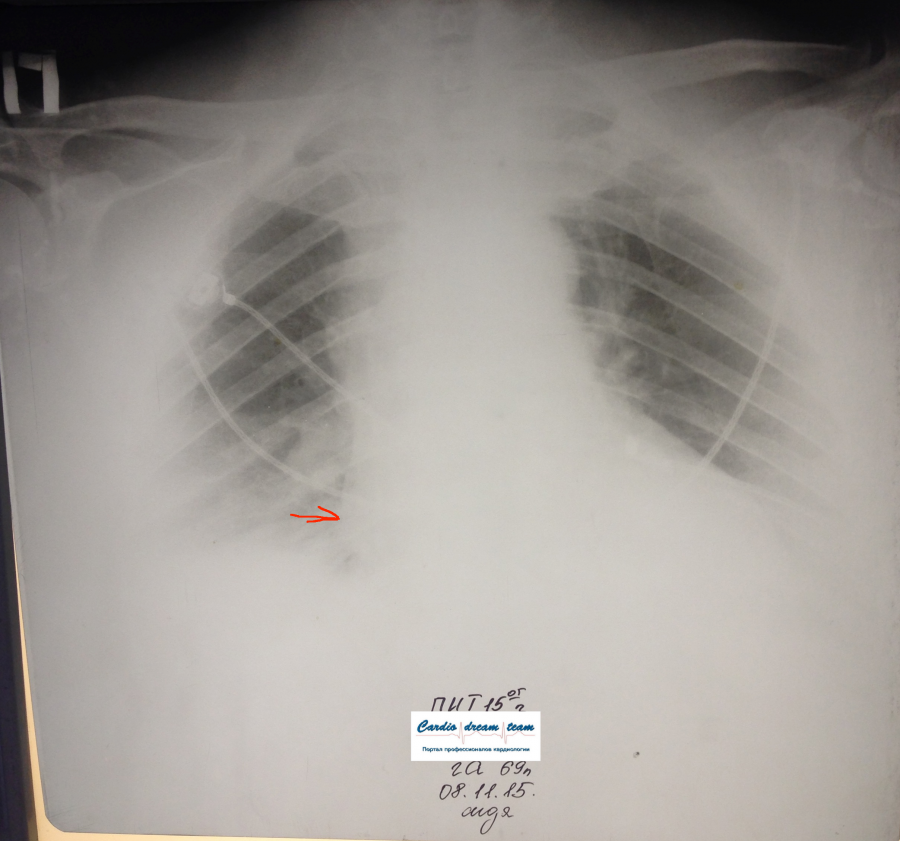

Стрелкой указано выпячивание правого предсердия.

Изображение